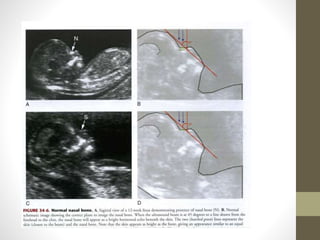

FACE AND NECK

WHAT TO SEE? IN FACE and

NECK

โ€ข 1.ORBIT

โ€ข 2.NASAL BONE

โ€ข 3.MAXILLA AND PRE MAXILLARY TRAINGLE

โ€ข 4.MANDIBLE

โ€ข 1.CYSTIC HYGROMA

โ€ข 2.OTHER SOLID OR CYSTIC MASSES